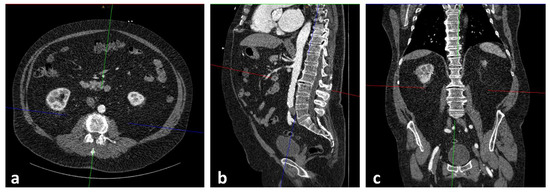

2.3. CTA Protocol and Measurement of PMAi for Sarcopenia Assessment